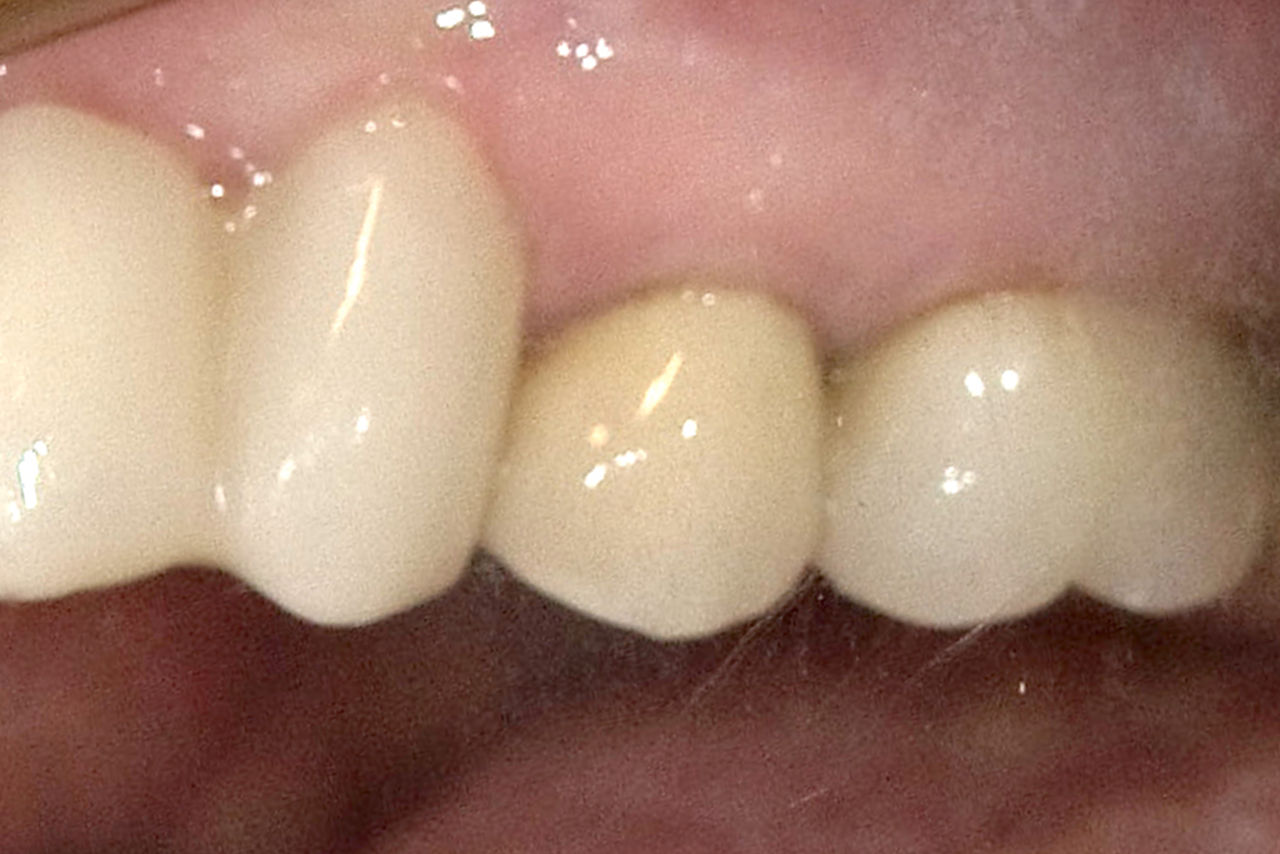

Second lower premolar, in 90 minutes

Katana Zirconia STML single crown

The restoration of this premolar was very well suited for the chairside treatment with zirconia and took only about 90 minutes in total. We were able to use full contour zirconia thanks to the wide range of shades available, achieving satisfactory results for aesthetic requirements.

Before: Discoloured tooth 45 as consequence of a previous root canal treatment.

After: Translucent zirconia crown with individualised finishing.

Dr. Gertrud Fabel

Munich, Germany